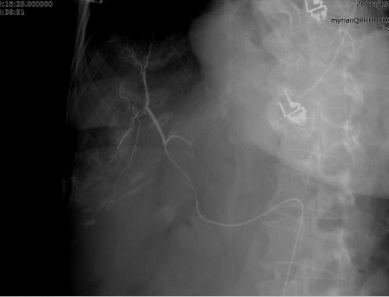

2. 呼吸门控(respiratory gating) 3. 实时肿瘤追踪 4. 控制通气(controlled ventilation) 事实上,几乎所有的肿瘤介入手术中,都是某种器械经皮直接进入人体内一个大小不一的解剖结构。为了帮助瞄准和器械的进入,在理想的情况下影像设备将提供实时的三维信息显示,包括靶标、介入器械和周围解剖的显示,或许在有些应用中还包括造影剂增强的或代谢活性区域的生理信息。

CT为病人提供进入的部分空间,并且可以间断的手术指导。CT透视是个接近实时的模式,但由于辐射限制只能少量使用【26,27】。像超声一样,CT也是一种平面引导技术,实时三维成像还没有完全集成到介入系统中。介入性磁共振成像系统已被开发【28】,但许多磁共振引导下介入设备,在今天仅仅用于诊断【29】。因为其空间还是是有限的,介入引导下的介入治疗通常还需要依赖于其他靶向技术。目前,所有三种断面的成像方式(超声,CT,和磁共振成像)的使用通常没有静脉注射造影剂,含有三维图像。